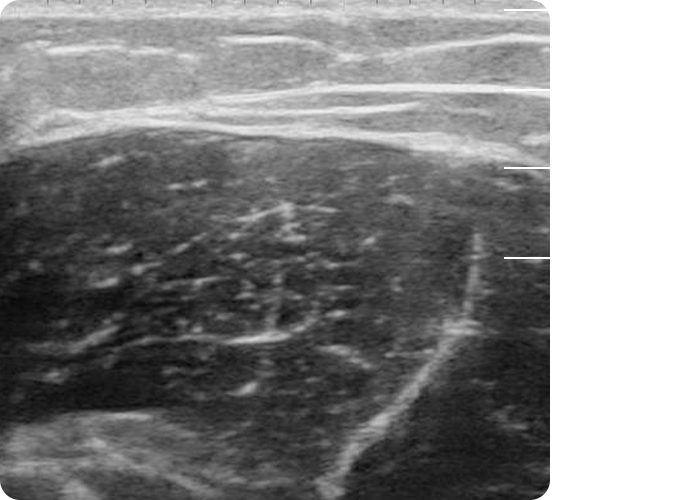

초음파로 공간을 먼저 확인하고,

초음파 공간 분석

힙 · 골반 · 힙딥 여유 공간 체크

초음파 힙필러는 피하지방의 깊은 층부터

안전하게 주입한 뒤, 그 위로 볼륨을 차곡차곡

쌓아가며 가능한 최대치까지 볼륨을 확보하는

방식으로 시술합니다.

초음파 바디필러 - - 구조 · 층 · 공간을 실시간 확인

- - 넣을 수 있는 곳 정확히 채움

- - 공간이 큰 쪽에 더 과감한 주입 가능

- 초음파 검진

- 초음파 분석 후 시술